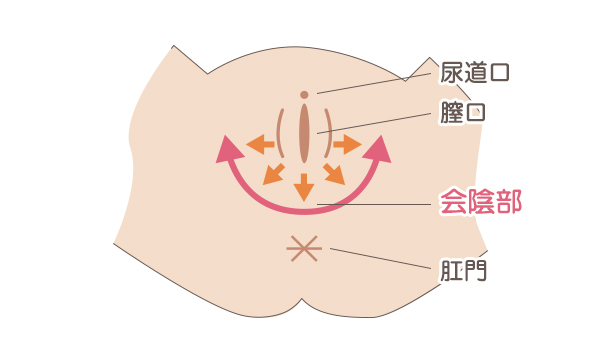

会陰切開について東京・世田谷での出産・分娩なら国立成育医療研究センター 産科。

会陰切開の傷跡が盛り上がり、痛い?会陰部分のお悩みを解消するにはスワンクリニック銀座。

会陰切開の痛みや傷跡はどういうもの?AMOMA公式 母乳育児向け専門ハーブティー、アロマ、マッサージオイルAMOMA naturalcare通販サイト。

会陰切開 をするタイミングは?痛みはある?切らない人もいる?会陰切開の不安と疑問に産婦人科医がお答えBaby-mo ベビモ。

会陰切開、吸引・鉗子分娩 出産のときの大切な医療処置たまひよ。

会陰切開今回は会陰切開の回復を早めるポイントをご紹介📢 "これからママになる 全ての女性をサポートしたい" そんな想いから 時期別 葉酸サプリmitas seriesシリーズは生まれました。  ̄ ̄ ̄ ̄ ̄ ̄ ̄ ̄ ̄ ̄ ̄ ̄ ̄ ̄ 妊活中に特化した温活もできるmitas妊娠中。

会陰切開の傷跡が盛り上がり、痛い?会陰部分のお悩みを解消するにはスワンクリニック銀座。

会陰部贅皮切除術銀座の美容外科・皮膚科ならルーチェクリニック。

会陰部、肛門のたるみの治療東京・銀座で産後、便秘による皮膚の傷跡、コンプレックスでお悩みならルクスクリニック。

会陰切開後の傷跡の痛み・盛り上がりでお悩みの方へ産婦人科専門医が解説博多駅直結の婦人科 ひよりレディースクリニック福岡博多。

妊娠に伴う正中線と出産時の会陰切開後に残る痛みについて蛭間医院。